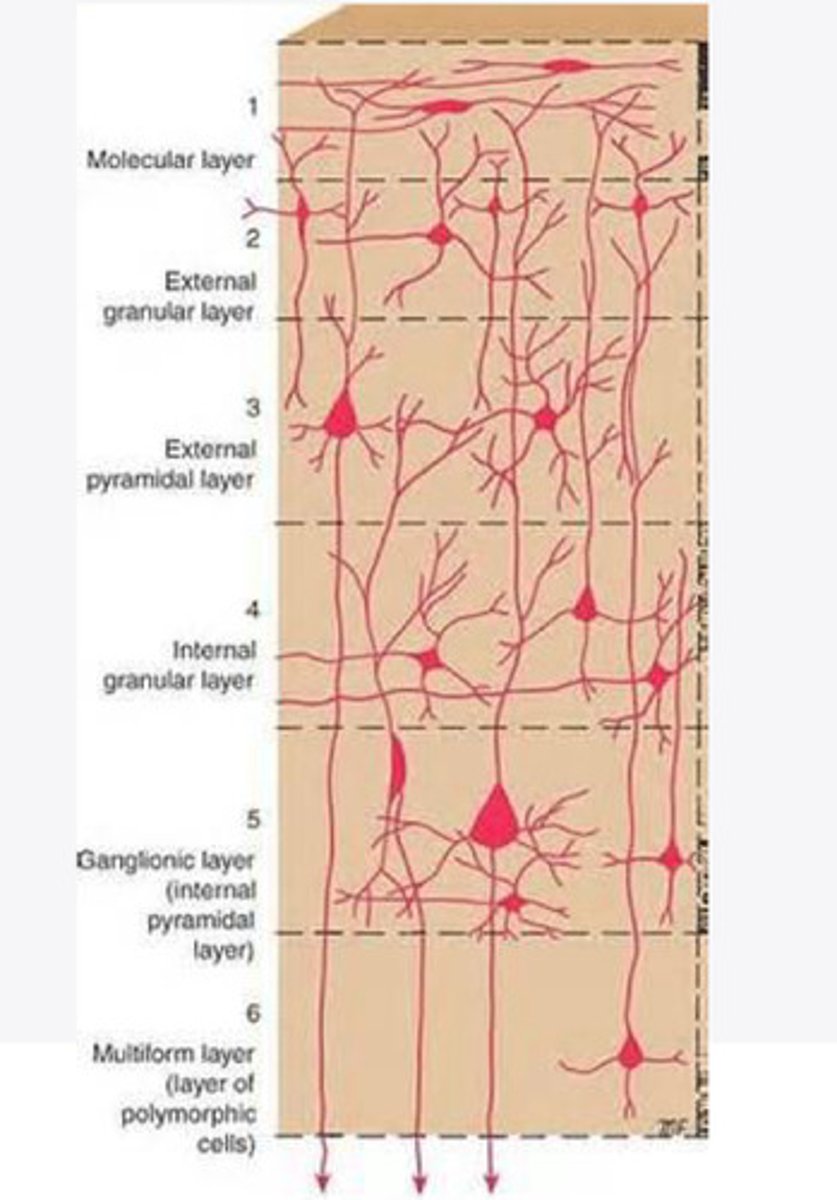

divided into 6 distinct layers, due to varying densities of cell body types within each layer

The cortex of the brain is divided into how many layers? Why is it divided into layers?

Layers of the cortex of the brain pic

2 and 4

What are the layers of the cortex that are associated with input?

3 and 5

What are the layers of the cortex that are associated with output?

molecular layer

What is the name of Layer 1 of the cortex of the brain?

very few cells

Does Layer 1 of the cortex have a lot or few cells?

receives dendrites from internal layers so it may actually function as a coordinating center where layers can communicate action

What does Layer 1 of the cortex do?

1

Every layer sends densities to Layer ____?

1

What layer serves as the "water cooler" of the brain?

external granular layer

What is the name for layer 2 of the cortex of the brain?

receives input from other cortical regions

What is the function of Layer 2 of the Cortex of the brain?

Stellate

What type of cells (stellate/pyramidal) would be most concentrated in Layer 2?

external pyramidal layer

What is the name for layer 3 of the cortex of the brain?

sends output to the other cortical layers

What is the function of Layer 3 of the cortex of the brain?

pyramidal

What type of cells (stellate/pyramidal) would be most concentrated in Layer 3 of the brain?

Layers 2 and 3

What layers are associated with association and commissural fibers?

Layer 3 - axons of cell bodies

Layer 2 - synapse into target areas in Layer 2

What part of the axons is in Layer 2/ in layer 3?

Layer 3 - external pyramidal layer

All axonal cel bodies for association and commissural fibers lie within what layer of the Cortex of the brain?

internal granular

** or called the striate cortex because it is so thick that you can see a line through this layer even in unstrained brain slides

What is the name for the 4th layer of the cortex of the brain?

receives input from the thalamus, geniculocortical layer, and other brainstem areas

What is the function for the 4th layer of the Cortex of the brain?

very thick within the vision, auditory, and somatosensory areas

Is Layer 4 thick or thin within SENSORY areas of the cortex?

Internal pyramidal

What is the name for Layer 5 of the cortex of the brain?

sends axons to the brainstem (corticobulbar) and spinal cord (corticospinal)

What is the function of Layer 5 of the cortex of the brain?

in motor areas of the cortex?

Where is layer 5 very thick in the brain?

the frontal lobe -- very motor heavy

What lobe of the brain will have a thick layer 5 of the cortex of the brain?

the multiform layer

What is the name of layer 6 of the cortex of the brain?

-sends axons back to the thalamus through corticogeniculate fibers

-modulates what information the thalamus sends to the cortex to control the strength of the signal received and modulate what you pay attention to

What is the function of layer 6 of the cortex of the brain?

no

Is layer 6 a motor layer?